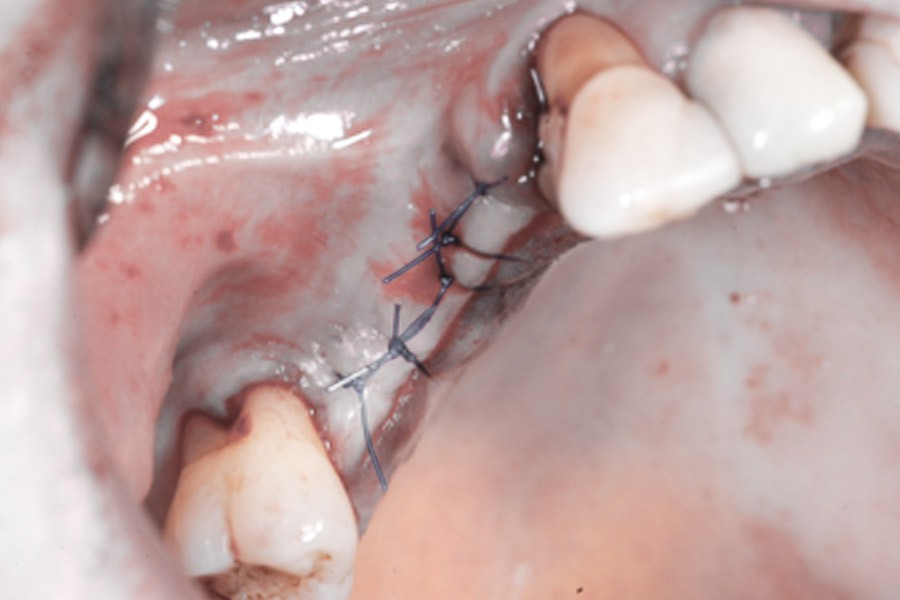

Zabieg odbudowy zębodołu powinno się wykonać możliwe jak najszybciej po usunięciu zęba. Jego celem jest odbudowa naturalnej objętości kości w miejscu utraconego zęba, a następnie szybkie wprowadzenie implantu. Najlepsze rezultaty uzyskuje się przy zastosowaniu biomateriału w formie bloczków kolagenowych lub granulatu, które dają trwałe efekty odbudowy oraz optymalną funkcję i estetykę odtworzonych koron zębów na wszczepionym implancie.

Procedury te są stosowane w sytuacji niedostatecznej ilości kości, skutkującej odsłonięciem gwintu, podczas gdy wszczepiamy implanty stomatologiczne lub też jako zabiegi poprzedzające ich wprowadzenie.​

Regeneracja kostna polega na umieszczeniu w rekonstruowanej okolicy materiału kościotwórczego oraz pokrycie go specjalną błoną zaporową, dzięki której regenerowany obszar chroniony jest przed wrastaniem tkanek miękkich. Po kilku miesiącach na skutek działania procesów regeneracyjnych i remodelujących materiał ulega przebudowie na pełnowartościową, własną tkankę kostną pacjenta, w którą bez obaw można wprowadzić implanty stomatologiczne. Obecnie istnieje wiele innych protokołów regeneracyjnych dla kości, uwzględniających zastosowanie różnego typu błon zaporowych, siatek tytanowych oraz uzyskanych i odwirowanych z krwi autogennych czynników wzrostu.

Membrana kolagenowa to cienka błona w formie prostokąta o różnych wymiarach, która ułożona w miejscu odbudowy ma za zadanie izolację nowo tworzącej się kości w ubytku od wnikania włóknistej tkanki podśluzowej, która zaburza proces osteogenezy.

Bloki kolagenowe używane są najczęściej do odbudowy geometrycznych, trójwymiarowych ubytków kostnych, których doskonałym przykładem jest zębodół po ekstrakcji zęba. Jest to jeden ze sposobów na procedurę „socket preservation”, czyli natychmiastową lub wczesną odbudowę zębodołów poekstrakcyjnych dla osiągnięcia optymalnych efektów estetycznej odbudowy protetycznej koron zębów na implantach.